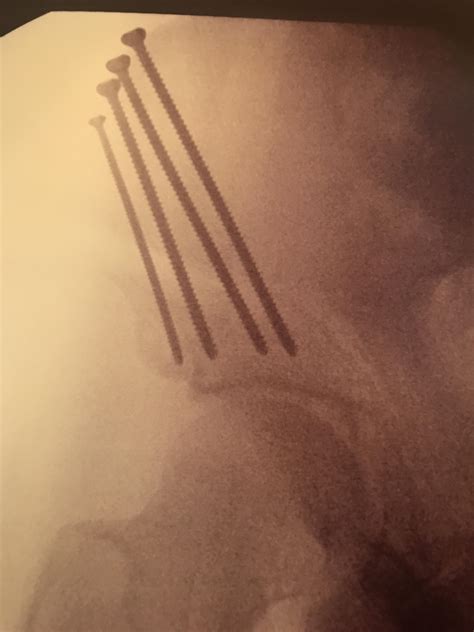

Revision Hip Surgery – Knee and Hip Website

Revision Hip Surgery – Knee and Hip Website